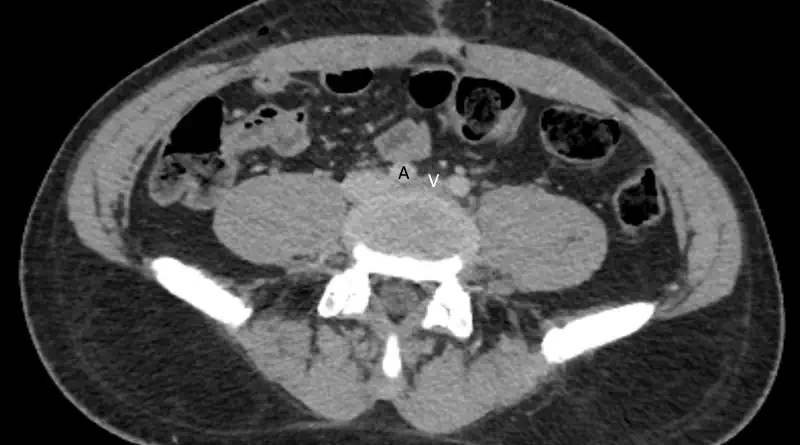

Most commonly, we will identify compression of the iliac vein without any symptoms. Veins are pliable structures. Basically, vein walls are soft. Look at the veins on the back of your hands. You should be able to compress them very easily. Similarly, when a person lies on their back in a CT scanner, chances are that the vein will appear compressed, even if it is not. In these cases, it is just the vein wall bending inward.

Assuming we suspect iliac vein compression, the next step is to prove the diagnosis. The two most useful imaging studies are CT and MRI.